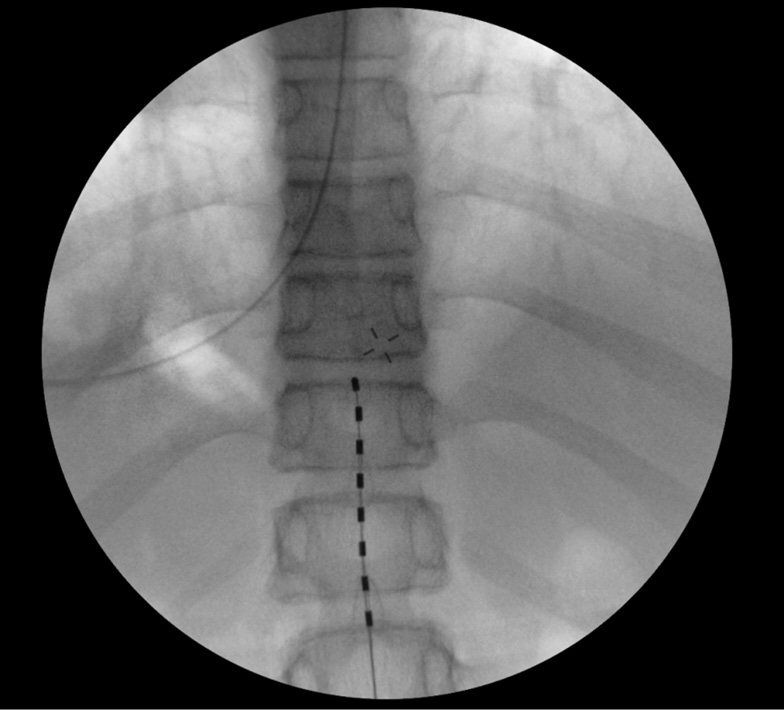

The surgery was performed to implant a permanent eight-junction cylindrical epidural electrode. The electrode was placed at the Th11–Th12 vertebrae level and the pulse generator was implanted in the right lumbar region using intraoperative radiography (Fig. 3).

Fig. 3. Intraoperative radiography and the position of the eight-junction epidural electrode at the Th11–Th12 vertebrae level